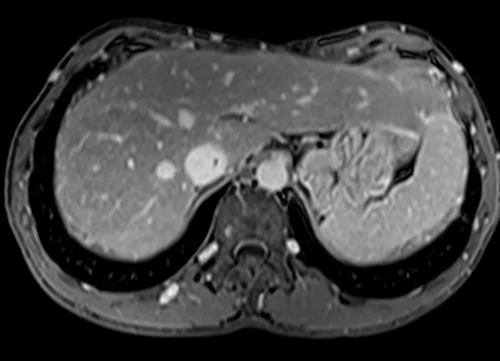

MRV abdomen axial t1 flash post contrast image 5 - MRI